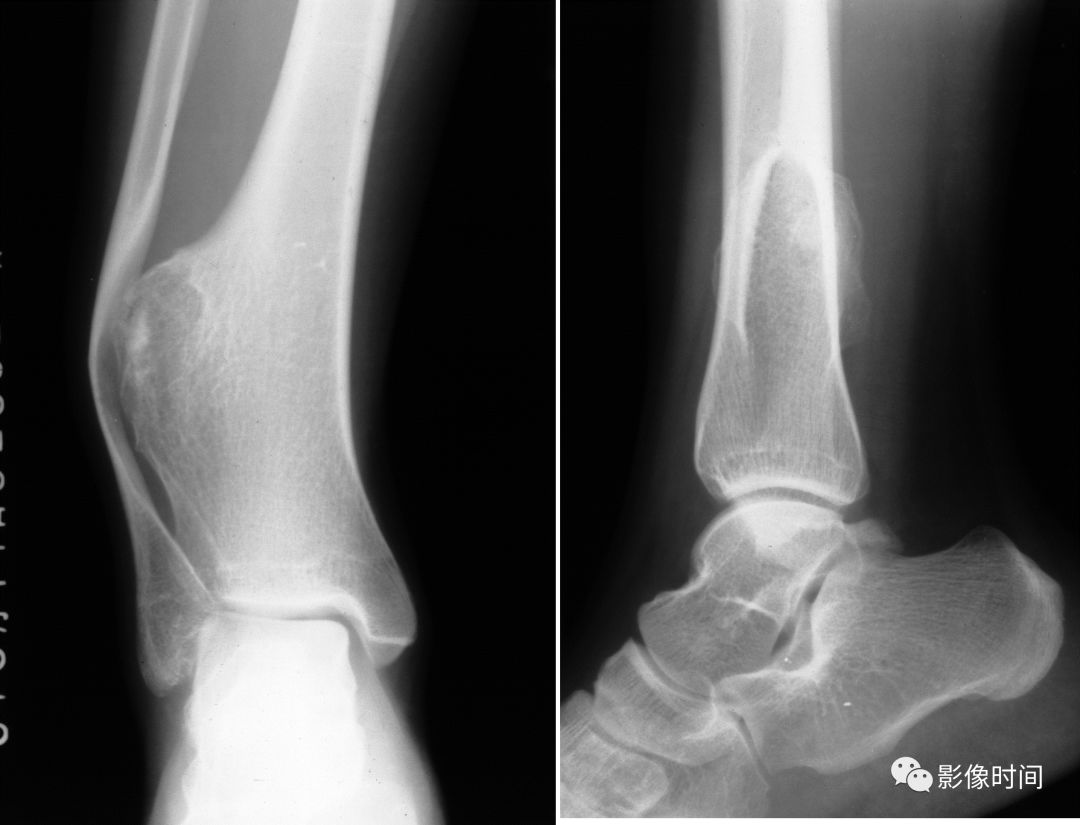

(一)地图样破坏  地图样破坏是指肿瘤组织在一个局部呈团块状生长造成界限清楚的骨质破坏(图 1、图 2、图 3、图 4)。

病灶可位于骨的中心或一侧部位,呈圆形、卵圆形密度减低区,与正常骨质分界清晰,边缘可有或无硬化带围绕,骨的形态无变化,病灶内可完全透亮或可见粗细不均、大小不等的残留骨嵴,内缘可光滑或呈分叶状压迹。

地图样破坏见于大多数良性肿瘤和肿瘤样病变如单纯性骨囊肿、骨纤维结构不良、血管瘤等、也可见于部分恶性骨肿瘤如骨转移瘤、骨髓瘤等。

图 1  地图样破坏:单纯性骨囊肿